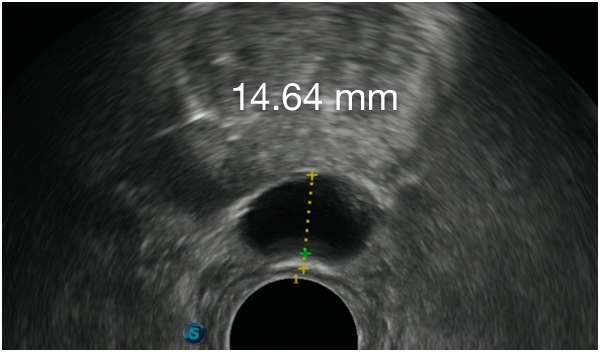

ACHIEVE CONSISTENT RESULTS

WITH BARRIGEL SPACER3,8,9

ACHIEVE CONSISTENT RESULTSWITH BARRIGEL

SPACER3,8,9

First Barrigel Spacer Cases - Consecutive Patients (Same Day)

TRUS images courtesy of Daniel R. Welchons, MD

Urologist; New York, United States

Results may vary.

DR. WELCHONS’ INJECTION TECHNIQUE